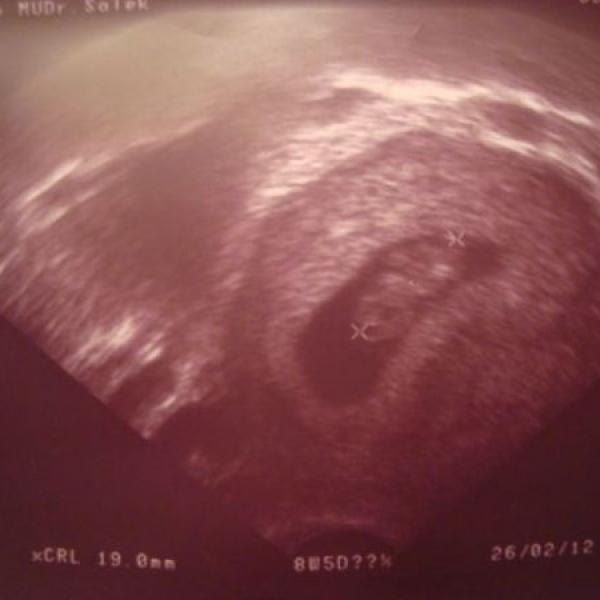

Ahoj,tak jsem byla v úterý na druhé kontrole,vše bylo v pořádku :h: .Napsal mi doporučení na genetiku,tak jsem včera byla v Praze na krvi a 18.8.

Ahojky,tak mám za sebou první kontrolu u doktora :*8*: .Bylo to rychlí,udělal mi jen vnitřní ultrazvuk a bylo to.Potvrdil,že je tam jen jeden plod(což se mi ulevilo)srdíčko bije :h: ,takže

Ahojky,mám takový dotaz ohledně týdnů těhotenství :///: .Počítala jsem si na těhu kalkulačce datum porodu atd. a moc to nechápu,vyšlo mi to takhle:Poslední MS jsem měla 23.5.2011,nejvyšší pravděpodobnost otěhotnění je 5.6.2011 (to sedí,dělali jsme to :*O*: 4.6.bylo to v sobotu v noci,takže skoro v neděli),ideální datum porodu je 26.2.2012,normální datum porodu je mezi 12.2.-11.3.2012,do porodu zbývá 35 týdnů,jsem přibližně 4+3.No ale když to počítám podle mýho kalendáře,tak jsem teprve 19 dní těhotná,tak jak to,že tady mi to píše 4 týden???